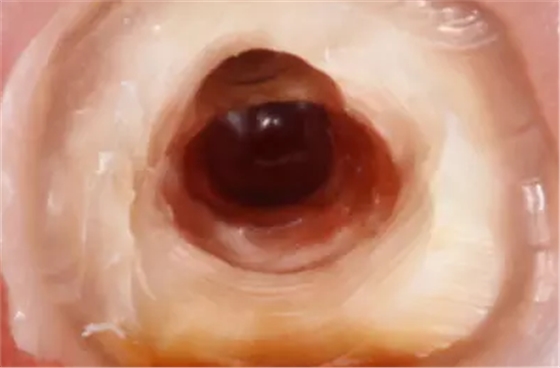

清理髓腔后,用中倍和高倍仔細(xì)查看穿孔的位置大小形狀和軟組織狀況。然后用小棉球?qū)⒏浇母芸诙氯?,以免異物掉入根管?nèi)。徹底清洗穿孔后,將調(diào)拌好的MTA材料充填到穿孔處,稍稍加壓,反復(fù)充填直到將穿孔填滿,使用小蒸餾水濕棉球整形,完成充填后,清理掉多余的材料,檢查外形。

然后用蒸餾水濕潤的小棉球封入髓腔至少24小時(shí),待MTA完全硬固后完成根管治療。穿孔修補(bǔ)和根管充填完成后,要進(jìn)行嚴(yán)密地冠部封閉,消除冠部的微滲漏。并進(jìn)行觀察3個(gè)月、6個(gè)月、12個(gè)月后再進(jìn)行永久修復(fù)。而且,術(shù)前應(yīng)向患者交代病情及預(yù)后情況和可能出現(xiàn)的問題。